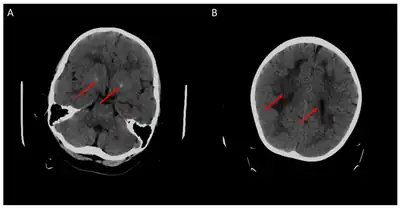

| 5-methyltetrahydrofolate is decreased in concentration in the human brain | |